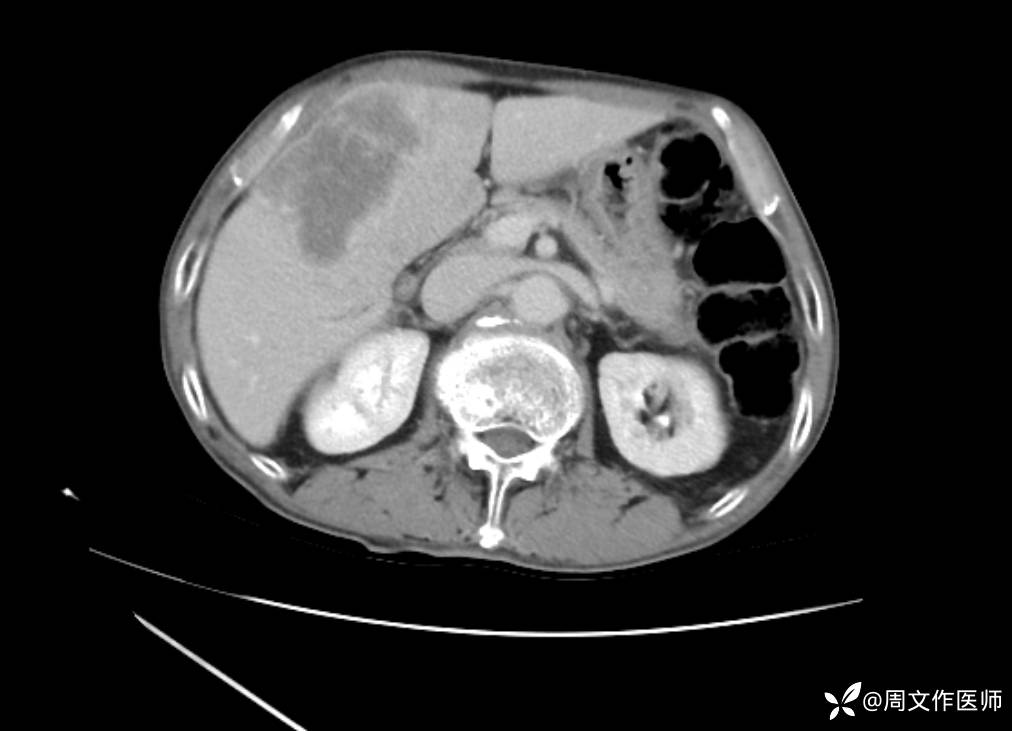

腹部增强CT检查